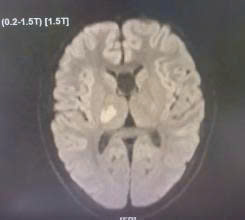

Ngày 13/9, Bệnh viện Nhi Thái Bình tiếp nhận một bệnh nhi nam 13 tuổi trong tình trạng đặc biệt. Em vốn khỏe mạnh nhưng bất ngờ xuất hiện yếu và tê bì nửa người trái, đi lại khó khăn.

Khi nhập viện, trẻ tỉnh táo, không sốt, không co giật, song vận động và cảm giác nửa người bị suy giảm rõ rệt. Từ những biểu hiện này, các bác sĩ chẩn đoán nhiều đến khả năng đột quỵ não ở trẻ em, một tình trạng nguy hiểm nhưng dễ bị bỏ sót bởi lâu nay phần lớn mọi người thường chỉ nghe và biết đến đột quỵ như một căn bệnh của người già. Thực tế, đột quỵ xảy ra khi mạch máu não bị tắc nghẽn dẫn đến thiếu máu não hoặc bị vỡ gây xuất huyết não, làm tổn thương các tế bào thần kinh. Khi tế bào não chết đi, các chức năng quan trọng như vận động, cảm giác, ngôn ngữ, thậm chí tính mạng của bệnh nhân đều bị đe dọa. Nếu người lớn tuổi có nguy cơ cao thì trẻ em, đặc biệt là những em mắc bệnh tim bẩm sinh, rối loạn đông máu hoặc bệnh lý mạn tính, cũng có thể bị đột quỵ bất kỳ lúc nào.

Hình ảnh chụp MRI não bộ của trẻ khi có dấu hiệu đột quỵ.